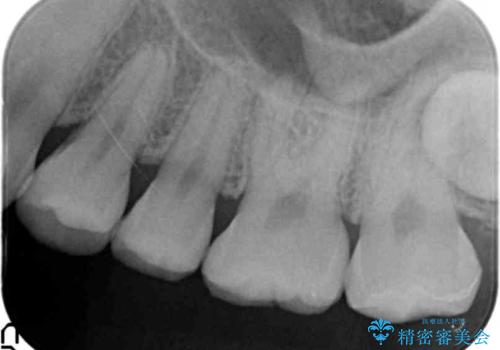

気づかなかった奥歯のう蝕 セラミックインレー 20代女性

患者様のご希望により、う蝕を丁寧に除去したのちセラミックインレーによる修復を行いました。

審美的な仕上がりと自然な咬み心地にご満足頂けました。

治療終了後も定期的にクリーニングとホワイトニングで通院して下さっています。

インレーの種類:セラミックインレー(e-max press)